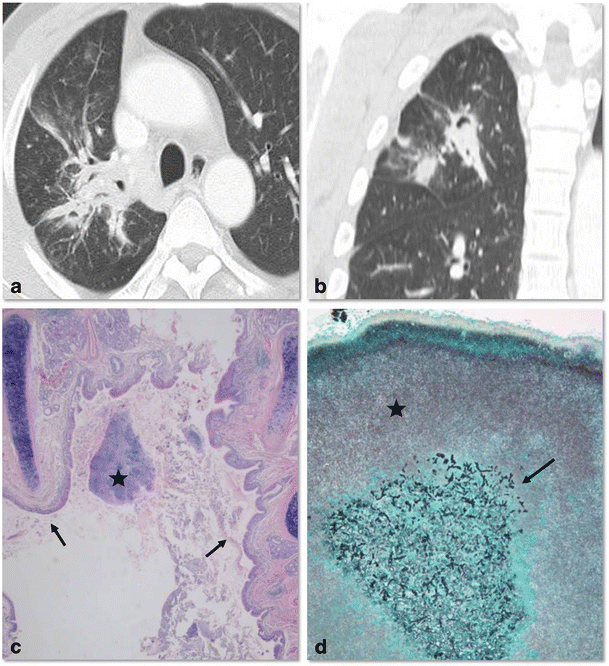

Визуализация и диагностика неинвазивного аспергиллеза с помощью КТ

Раздел: Необычные решения